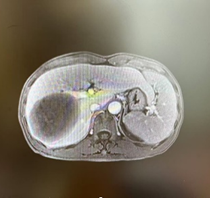

新辅助(两次HAIC和两个周期靶免治疗)后CT

新辅助(两次HAIC和两个周期靶免治疗)后MR

由于病人一般情况较好,肝功能良好(Child-pugh A级),经多学科会诊临床确认肿瘤为IIb期肝细胞癌,属于可切除性肝癌,但存在高危复发因素,建议先行新辅助治疗后手术切除。经两次肝动脉关注化疗(HAIC)(奥沙利铂+5-Fu+亚叶酸钙方案)和两个周期的靶向免疫治疗(仑伐替尼+帕博利珠单抗方案),第二次介入造影是肿瘤血供不明显,第二次介入治疗4周后复查CT提示肿瘤缩小不明显但坏死征象明显,经MRI证实仍有少许血供,于是经多学科会诊后决定行前入路右半肝切除术。